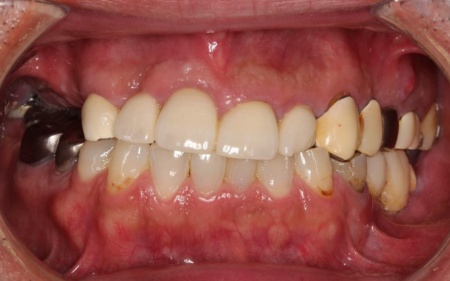

治療前

拝見したところ、上の歯は1本も残っておらず、下の歯もほぼ失われているため食べ物を噛むことが難しく、加えて見た目の美しさも損なわれている状態です。

また残っている下の歯は、左右1本ずつ(右下第1小臼歯/4番、左下第2小臼歯/5番)以外は指で掴むと抜けてしまうほどグラグラと揺れており、抜歯が必要であると診断しました。